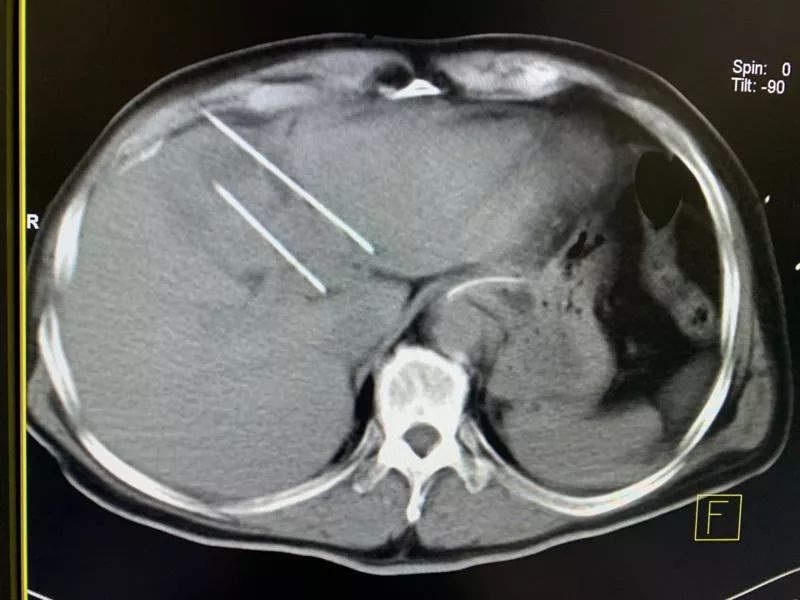

所以,复大的专家团队决定对郑先生采取纳米刀消融,对肝上的肿瘤和门静脉癌栓都进行了消融。据郑先生的主刀医生牛立志教授介绍,郑先生门静脉的左枝和主干已经填满了癌栓。手术最困难的是,门静脉主干的穿刺面临着血管出血的可能性,包括对门静脉的损伤。

但是对于这种情况,纳米刀的优势就体现了出来。纳米刀的针非常细,只有一毫米,可以直接穿刺到血管里,而不会造成血管破裂出血这样的情况。